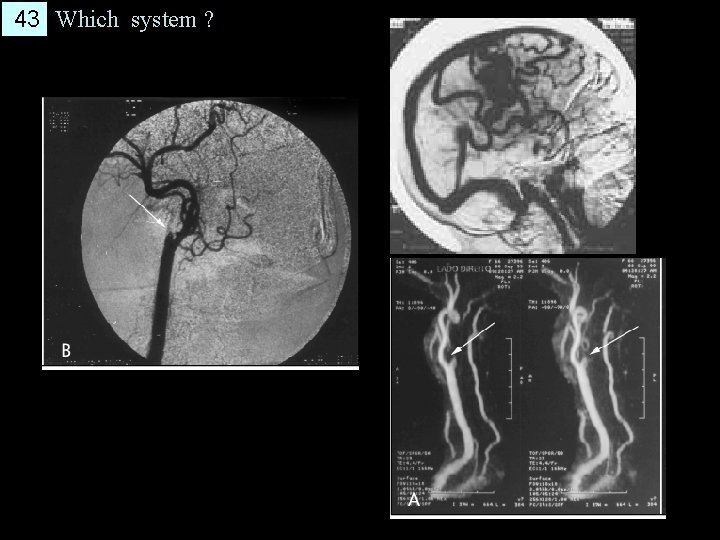

43 Which system ?

44